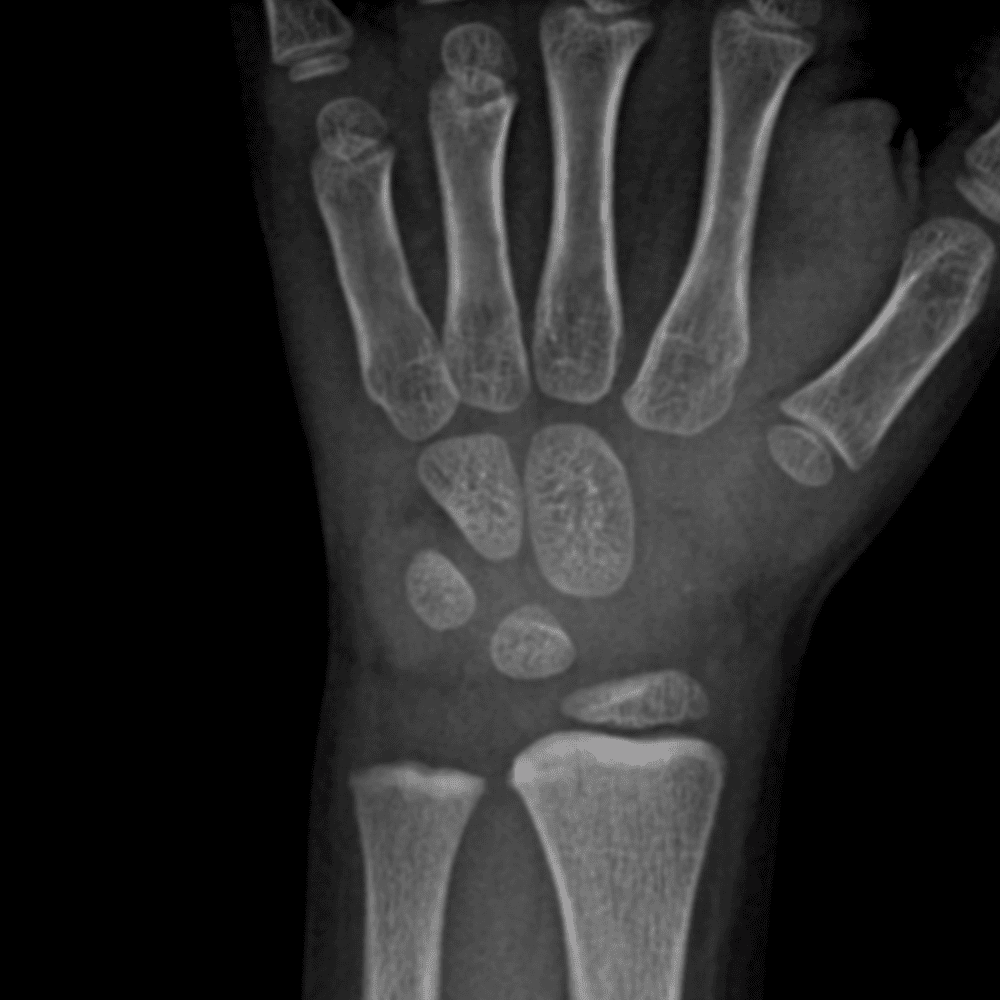

Simulates call by including subtle or difficult cases and some normals.

30 cases